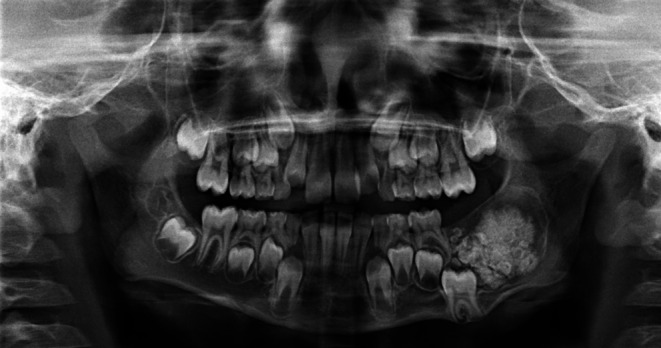

Methods: We present a case of an 8-year-old child with a slowly progressive swelling in the lower left mandible. Next-generation sequencing (TSO500 panel) was performed.

Results: Panoramic radiography revealed an odontogenic tumor; therefore, a transoral enucleation was performed. Pathological microscopic examination confirmed the diagnosis of AFO, and next-generation sequencing detected an FGFR1 mutation.